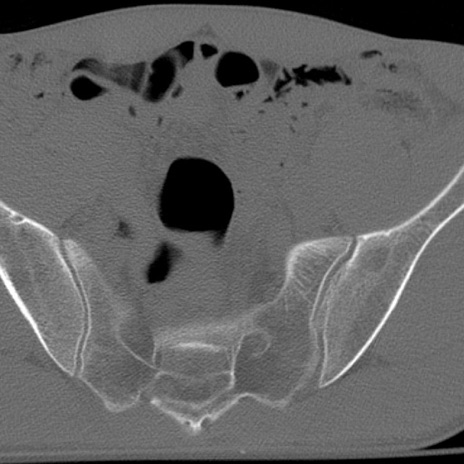

症例3 腰椎CT(横断像)

腰椎CT